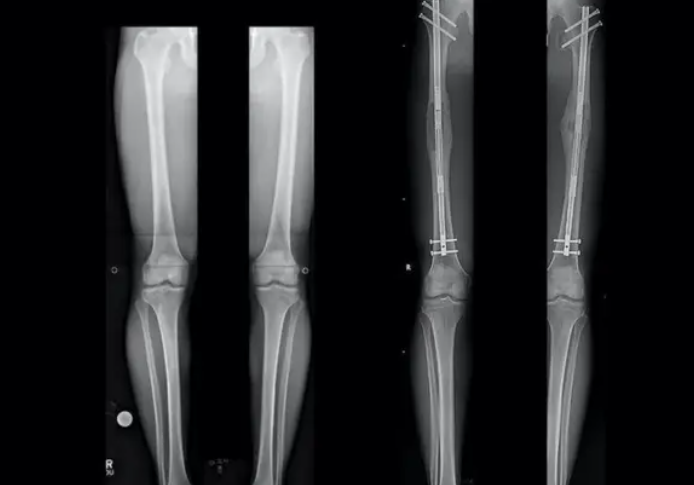

所謂**“斷骨增高”**,就是使用截骨術,切斷小腿或大腿骨,把已經閉合的骨生長線重新“打開”,並在體外安裝一種具有牽伸作用的肢體延長器,利用骨頭癒合的機能,強行拉伸肢體,每天可以長高0.5毫米-1毫米。

這種手術非常痛苦,患者需要忍受多根鋼針扎穿雙腿,恢復過程中的更是每天痛到覺都睡不着。且手術風險極高,可能導致嚴重感染、腿骨神經受損,因為個人體質問題,有一定概率出現腿骨生長中斷等,那麼等待你的就是終身殘疾。在世界上絕大多數國家,“斷骨增高”都被明令禁止用於整形目的,僅限於嚴重身體畸形者的治療。